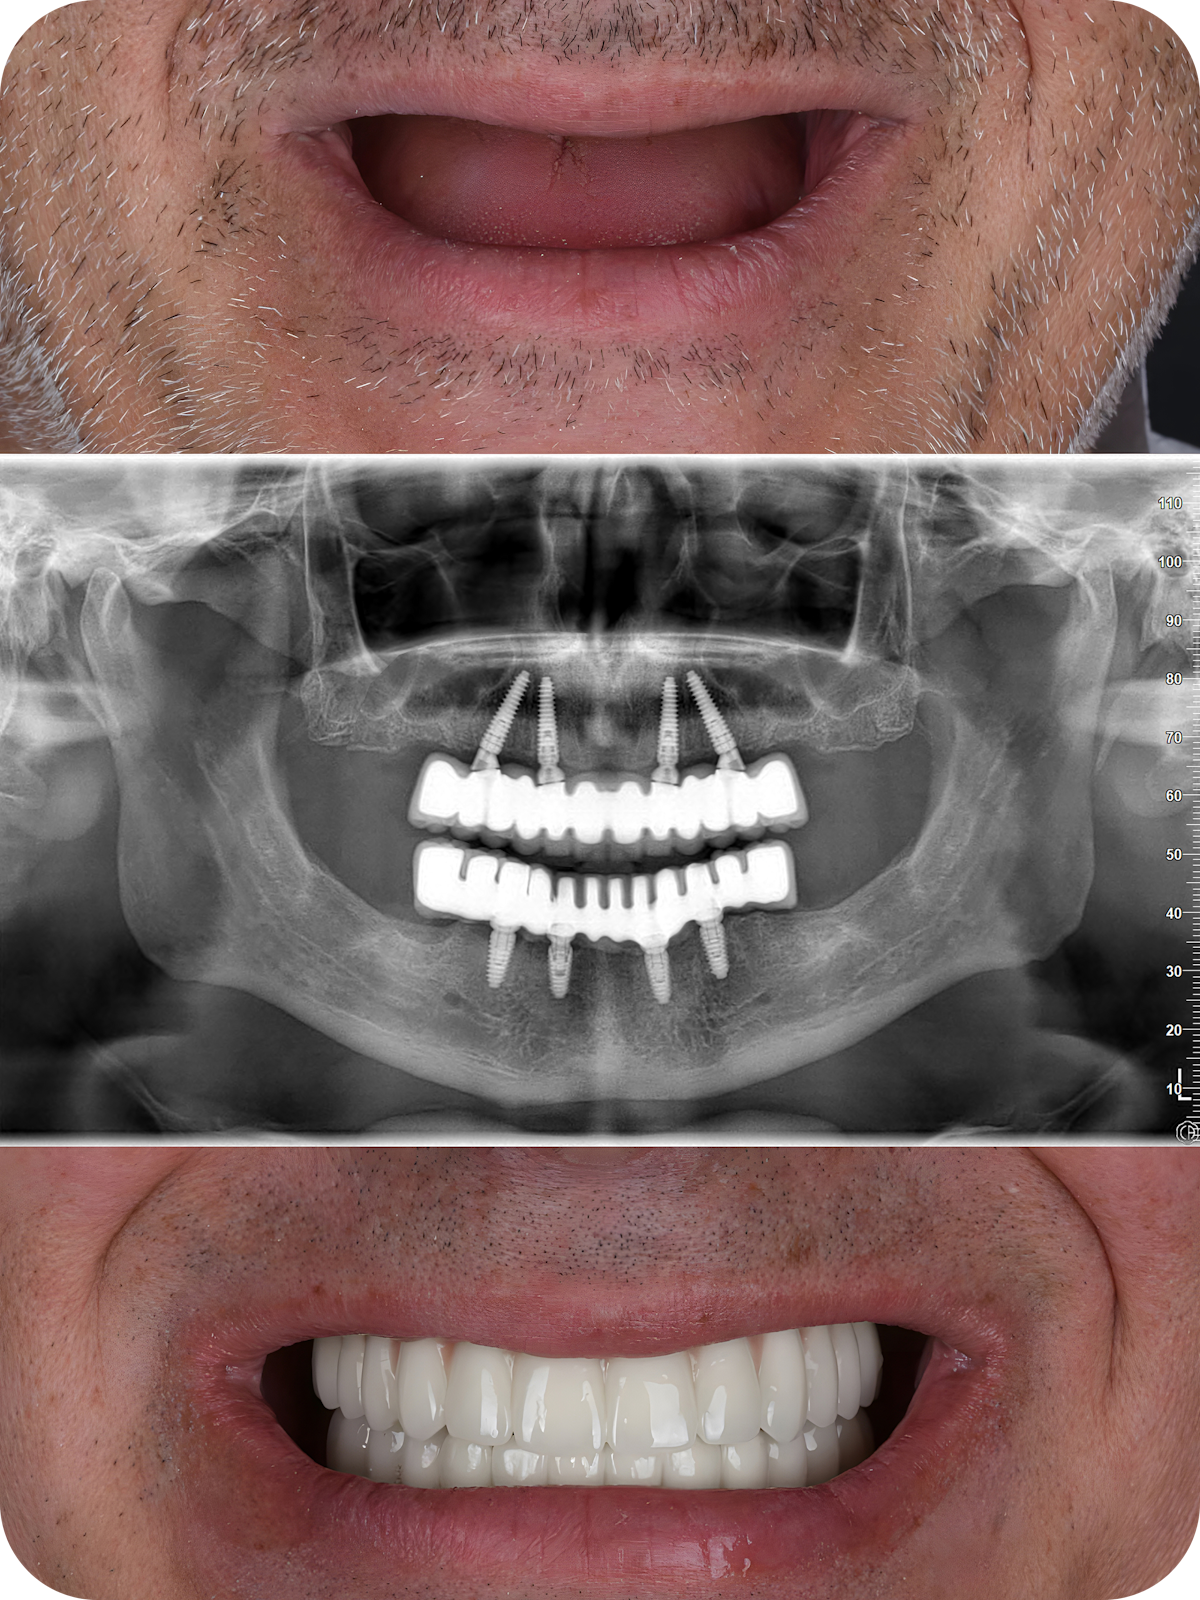

Patients with extensive tooth loss often find simple pleasures like eating and speaking difficult. This can greatly impact your quality of life and your confidence. At Eva Urena DDS, we are here to help with expert All-on-4 dental implant care. This life-changing dental treatment can restore the health, function, and appearance of your smile, often without preparatory bone grafting.

All-on-4 dental implants use just four implant posts. Two of the dental implants are placed at strategic angles to maximize contact with your existing bone material. This allows many patients to skip the bone grafting and experience a healthy and beautiful smile faster.

All-on-4 dental implants provide the same great benefits as traditional dental implants. The key differences are only four implant posts are used per arch, and two of those implants are placed at an angle. This method allows patients with mild to moderate jawbone atrophy to reap the benefits of dental implants and stop the deterioration process.